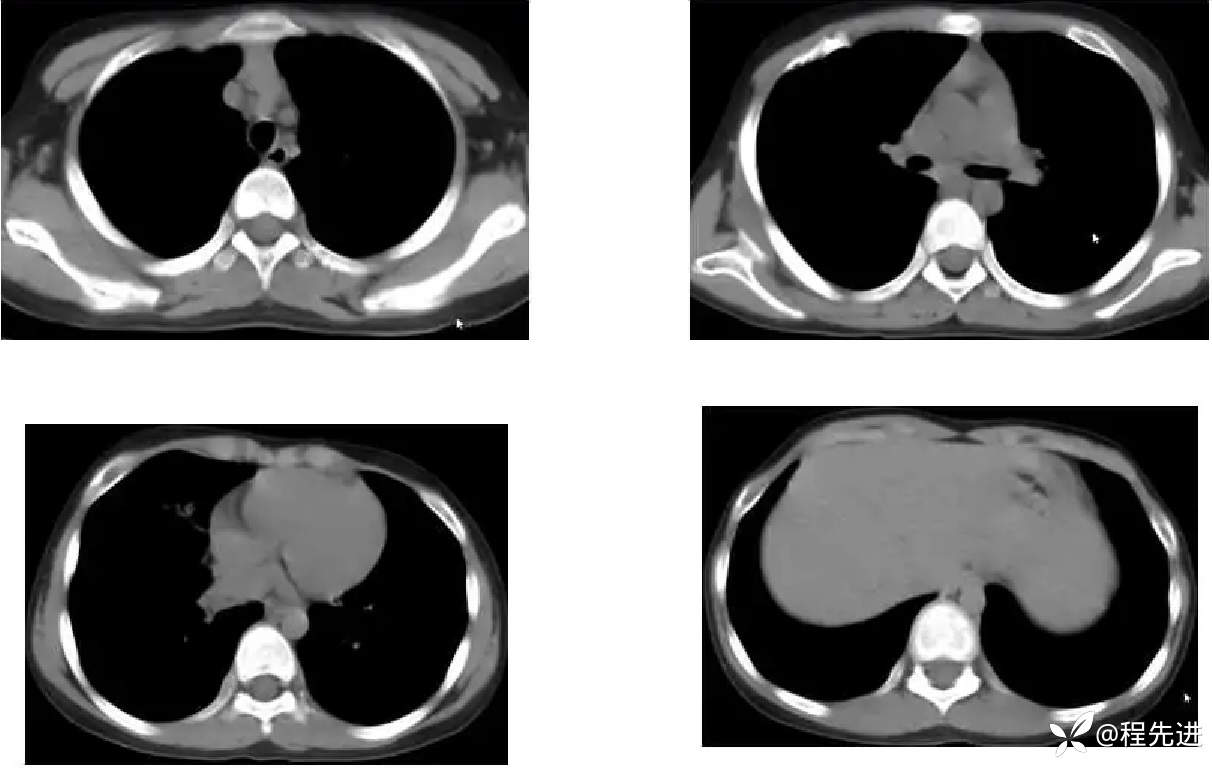

患者性别:男

患者年龄:11岁

简要病史:受凉后发热3天

既往史:生长发育迟缓

胸部CT: